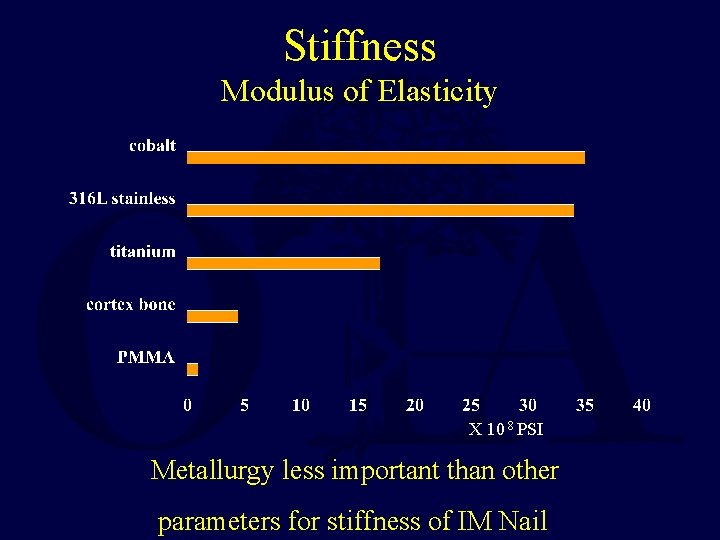

Stiffness Modulus of Elasticity X 10 8 PSI Metallurgy less important than other parameters for stiffness of IM Nail